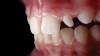

(14.) Photograph of fractured right lateral incisor taken with a smartphone and an EALS device during patient presentation for emergency treatment shown with accompanying radiograph.

Figure 14

(15.) Photograph of fractured right lateral incisor taken with a smartphone and an EALS device during patient presentation for emergency treatment shown with accompanying radiograph.

Figure 15

Emergency visits are a common and unpredictable occurrence at nearly all dental practices (Figure 14 and Figure 15). When an emergency occurs, the patient's provider may not always be available to evaluate and initiate treatment. In a similar manner, new patients of record frequently present with oral conditions that require the attention of a dental specialist who may only be available at another clinic (Figure 16 and Figure 17). For many of these patients, immediate access to care may be limited, and if a patient is experiencing discomfort, time will be a critical factor in regard to initiating a proposed plan of action. The use of a smartphone with an EALS can allow the clinical staff to rapidly acquire intraoral photographs or a video and transmit these images and other information via encrypted text message or secure e-mail to anywhere in the world for immediate consultation. The combination of telecommunications and dentistry is known as teledentistry,13which has been shown to impart significant benefits to patients and providers in the fields of oral medicine,14 oral and maxillofacial surgery,15 endodontics,16 prosthodontics,17 periodontics,18 pediatrics,19 orthodontics,20 and oral hygiene.21